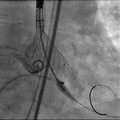

根部造影

导丝跨瓣

输送器定位

释放瓣膜

瓣膜释放完毕